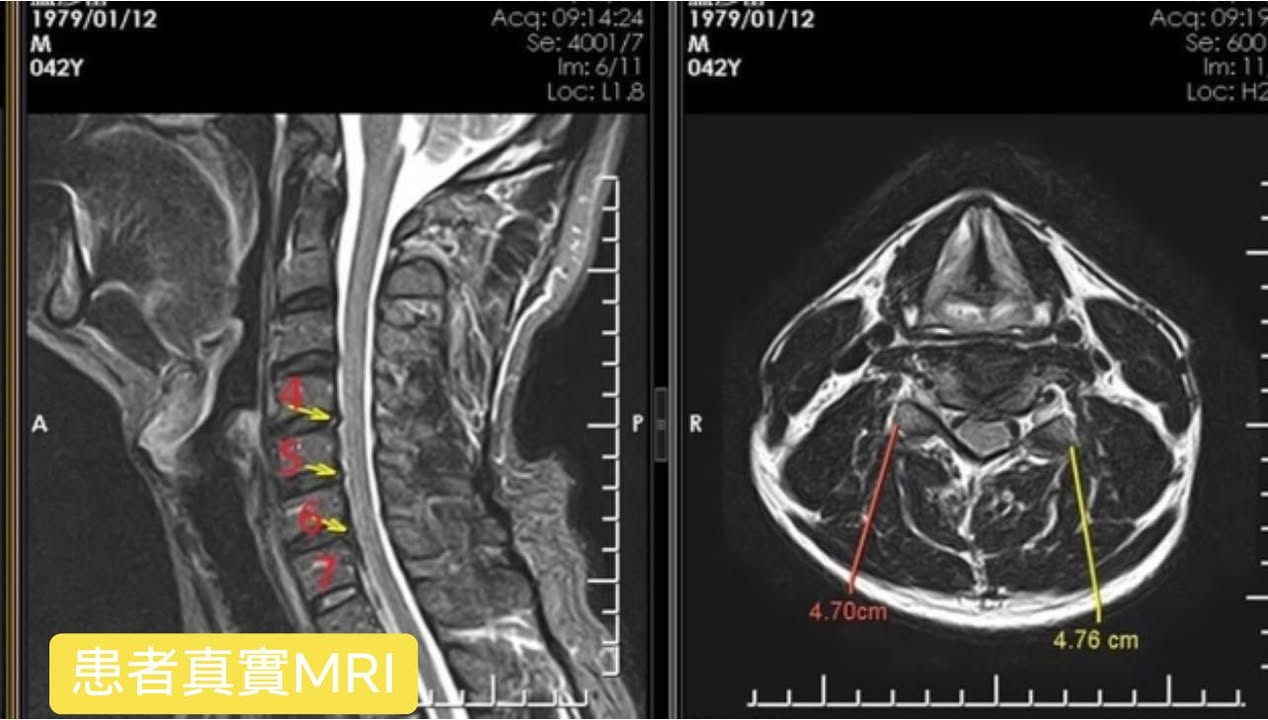

Cervical Spine Treatment Cases 頸椎治療案例 頸椎過直會導致肩膀酸痛嗎?中醫微創針刀療法成功改善頸椎弧度 2021.11.03 頸椎骨刺導致步態不穩、半身麻痛,一定要開刀嗎?中醫針刀治療100天改善實例公開 2021.10.07 冷水刺痛全身、下肢異常竟源自頸椎壓迫?MRI對比揭示非手術療法改善實證 2021.10.08 伏地挺身突然做不到?竟是C6C7頸椎壓迫導致神經肌力減退!中醫微創療法10週改善 2021.09.11 低頭族小心!頸椎滑脫竟導致長期頭痛肩痛與睡眠障礙|12次中醫微創治療成功矯正滑脫 2021.07.16 醫案實證:術後再發的脊髓壓迫症也能靠中醫療法改善 2021.07.10 手術後腳還是麻?頸椎開刀半年症狀未解,靠中醫微創8次改善右腳無力與手麻! 2021.06.30 狂送急診四次竟查不出病因!胸悶心悸原來是頸椎壓迫,靠針刀微創13次改善 2021.06.09 後縱韌帶鈣化壓迫脊髓!步態不穩、手腳麻木竟可逆轉?14週22次針刀治療真實見證 2021.05.06 什麼是中樞型脊髓型頸椎病?症狀、診斷與治療全解析 2021.05.28 神經根型頸椎病症狀解析:肩麻、手痛與肌肉萎縮 2021.04.16 嚴重心悸胸悶竟是頸椎問題!交感神經型頸椎病針治2次症狀明顯改善|真實病例與患者疼... 2021.04.07 從心悸胸悶到手麻夜痛難眠,她竟是頸椎壓迫!真實MRI對比見證中醫逆轉勝療效 2021.04.04 從手腳無力到步態不穩,他竟是頸椎脊髓型壓迫!三個月密集針刀療法逆轉勝|台北蔡大哥... 2021.03.31 頸椎椎間盤突出要一次動四節嗎?手術vs.保守治療完整解析 2021.03.27 ← 上一頁 2 3 4 5 6 下一頁 →